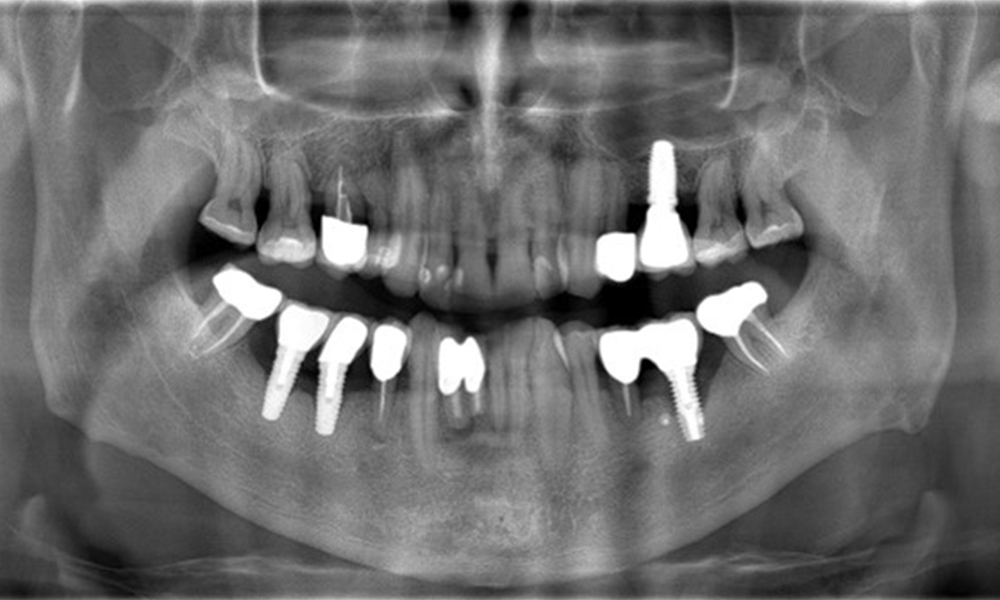

A 52-year-old patient presents at a preventive care session. The patient has no systemic disease and is not taking any medication. He has had various dental treatments and also has two active carious lesions. In addition, the patient has four implants (2nd, 3rd and 4th quadrants). He is revealed to have early periodontal disease (stage IV, grade B). His periodontal condition is stable; a probing depth of Probing depths (ST) of 5 mm is only evident at the implant in region 36. Gingivitis is also identified.

Previous treatments: multiple ceramic restorations, four implants (2nd, 3rd, 4th quadrants)

The patient has no particular risk factors with specific dental implications in his medical history. The key factor, therefore, is the requirement in terms of oral health. In this respect, there is evidence of a probing depth of 5 mm at the implant in the 3rd quadrant and, on the X-ray image, increased bone loss. The patient also has currently stable early periodontal disease and two active initial carious lesions.